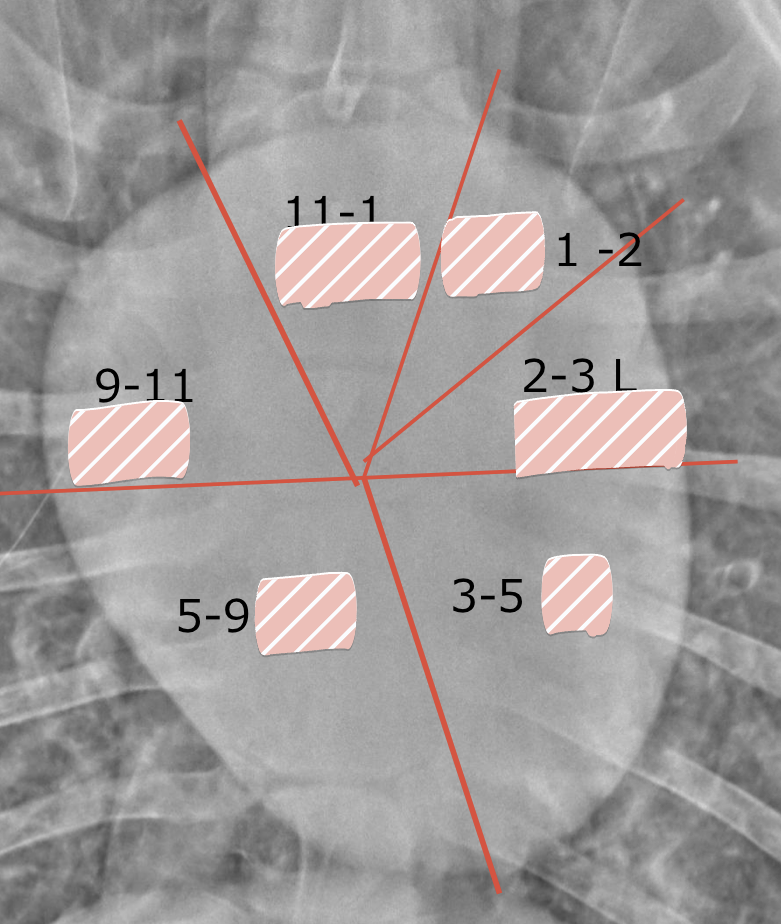

Use this image with this question. Using the provided feline images, how would you describe the cardiac silhouette?

Which is the appropriate size of a feline cardiac silhouette?